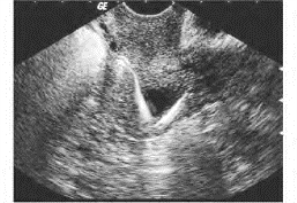

1.节育器嵌顿 因节育器过大或接头处断裂等原因,致其部分或全部嵌入肌层内,声像图表现为节育器位置偏于宫腔一侧,不在中心部位,且周围无子宫内膜呈现的低回声晕围绕(图33-19A)。

图33-19A 节育器断裂声像图